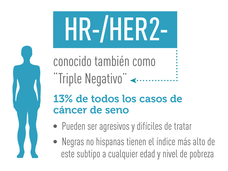

Concentración en una adicción en cáncer de seno triple negativo

Un nuevo método para interrumpir los genes que promueven la formación y diseminación de tumores puede prometer que se pueda tratar un tipo de cáncer de seno que es agresivo y difícil de tratar.